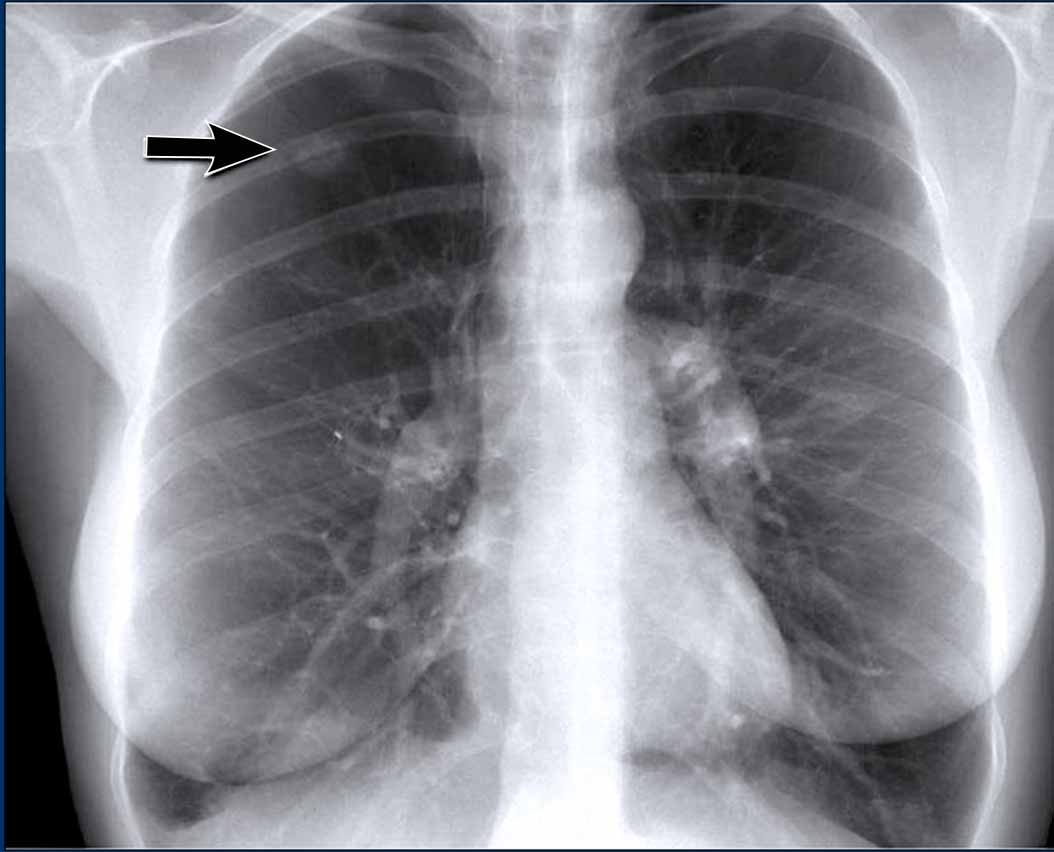

Hidden area (5): Mass Behind the First Rib

In some patients, an accessory joint at the anterior aspect of the first rib may simulate a mass, as we learned earlier.

However this area is also a "hidden zone", where true lesions can be masked.

• In this case, a small lung carcinoma was obscured by the left first rib on the PA view.

• On the lateral film, the lesion is visible in the retrosternal space.

Continue with the PET-CT...

Subsequent PET-CT imaging confirmed a hypermetabolic tumor (arrow), with metastases to the bone and liver.

• Diagnosis was confirmed via biopsy of an osteolytic metastasis in the iliac bone.